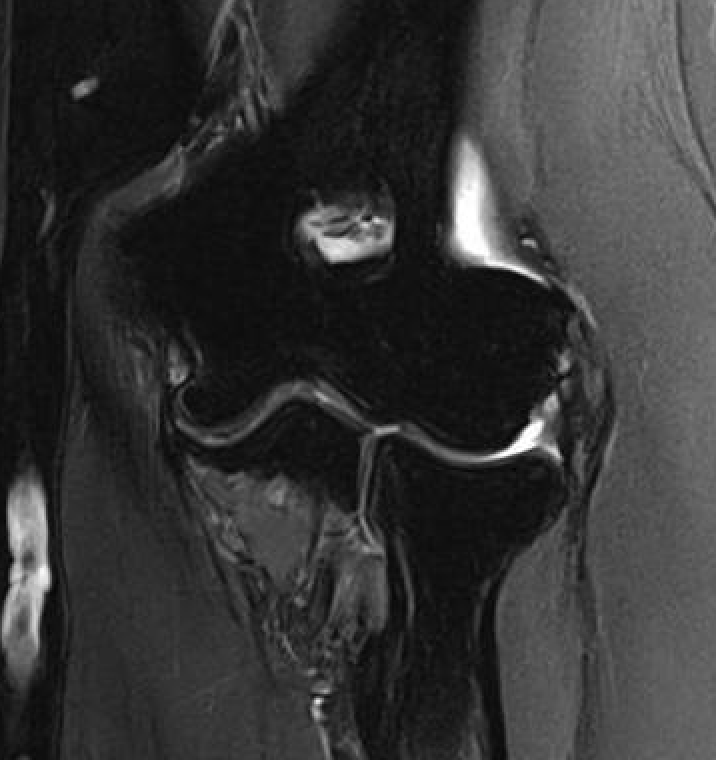

MRI

High grade partial tears of ECRB on lateral eipcondyle

Tendonopathy of the common extensor origin, with thickening and high grade tear partial tear

Tendonopathy of the common extensor origin, with thickening and high grade tear partial tear